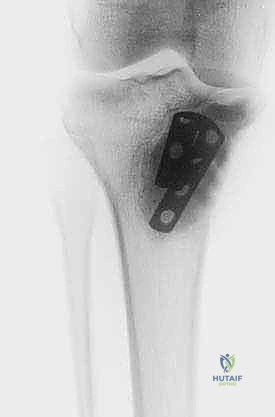

الخطوة الخامسة: إعادة البناء والترميم (Reconstruction)

بعد القضاء على الورم، يتبقى تجويف فارغ داخل العظم. يقوم الدكتور هطيف بملء هذا الفراغ إما باستخدام ترقيع عظمي (Bone Graft) أو الإسمنت العظمي (PMMA - Bone Cement). الإسمنت العظمي له فائدة مزدوجة: فهو يوفر دعماً ميكانيكياً فورياً للعظم، والحرارة الناتجة عن تصلبه توفر تأثيراً إضافياً قاتلاً للخلايا الورمية المتبقية.